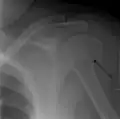

A fracture of the greater tuberosity as seen on AP X ray -

A fracture of the greater tuberosity of the humerus -

Fracture of the greater tuberosity of the humerus -

Multi-fragmented, or comminuted fracture of the proximal humerus with involvement of the greater tuberosity -

Proximal humerus fracture -